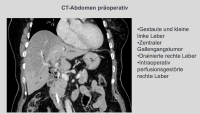

En el caso demostrado, se trata de un tumor de conducto biliar estenosante en la bifurcación hepática Bismuth IIIb, que fue diagnosticado mediante MRCP, ERCP y citología por cepillado.Una resección derecha extendida no era viable debido a la atrofia del lóbulo hepático izquierdo. Por lo tanto, se recurrió a la extirpación de los segmentos hepáticos 1,4,5 y 8 con preservación de los segmentos laterales 6,7 y 2,3, especialmente porque la bifurcación de la vena porta y la arteria hepática izquierda no aparecían infiltradas en la imagen morfológica.